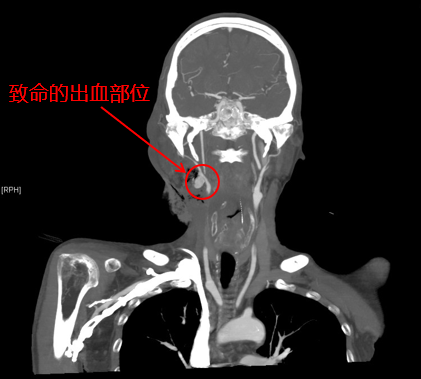

清华长庚多学科联合 为晚期肿瘤患者抢回来一个春节